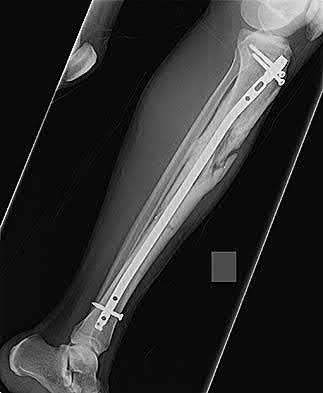

Which bone morphogenetic protein (BMP) is FDA-approved as an alternative to autograft for the treatment of acute, open tibial shaft fractures stabilized with an intramedullary nail?

Recombinant human Bone Morphogenetic Protein-2 (rhBMP-2) is FDA approved for use in acute, open tibial shaft fractures stabilized with an intramedullary nail. rhBMP-7 (Osteogenic Protein-1 or OP-1) previously had a Humanitarian Device Exemption (HDE) for recalcitrant long bone nonunions but is no longer commercially available in the US for this indication.